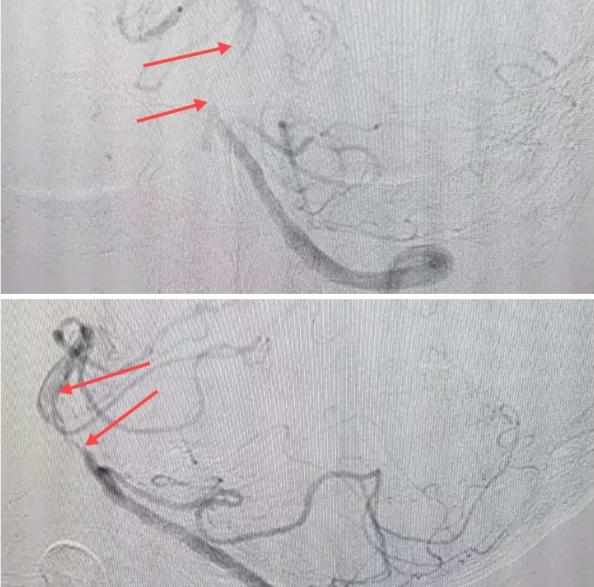

在經(jīng)造影后,主刀醫(yī)生腦一科副主任楊慶堂發(fā)現(xiàn)患者基底動脈下段重度狹窄且狹窄段以遠有大負(fù)荷血栓,其狹窄處考慮為動脈夾層,手術(shù)難度及風(fēng)險較大。楊慶堂副主任在彭壯副主任醫(yī)師的協(xié)助下運用spaceman(太空人)技術(shù),中間導(dǎo)管抵近血栓抽吸配合支架拉栓,成功開通血管。再次造影可見基底動脈管腔明顯增寬,遠端血管顯影良好,且等待20分鐘后造影仍顯示血流通暢。楊慶堂副主任考慮到本次手術(shù)時間不宜過長,現(xiàn)患者基底動脈及分支前向血流維持良好,給予其抗栓藥物應(yīng)用后結(jié)束手術(shù),并建議患者3個月后復(fù)查造影,明確其基底動脈夾層情況。

取栓后血管管腔增寬,前向血流良好